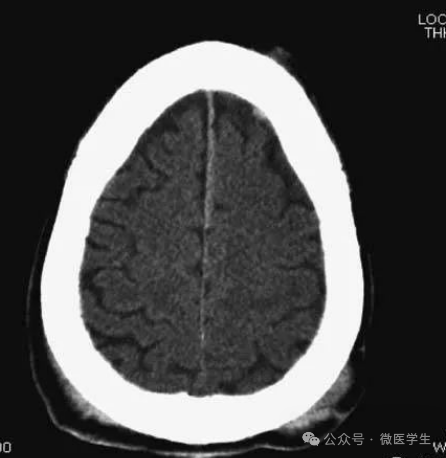

由额、颞、枕叶构成,两侧侧脑室体部之间为透明隔,外侧为尾状核和体部。侧脑室后角(枕角)可不对称,室内可见脉络丛钙化。中线处可见大脑纵裂池和大脑镰。

内侧壁侧脑室体部被胼胝体分开,侧脑室体部的外方为顶叶,顶枕沟及中央沟将大脑为为额、顶、枕叶。